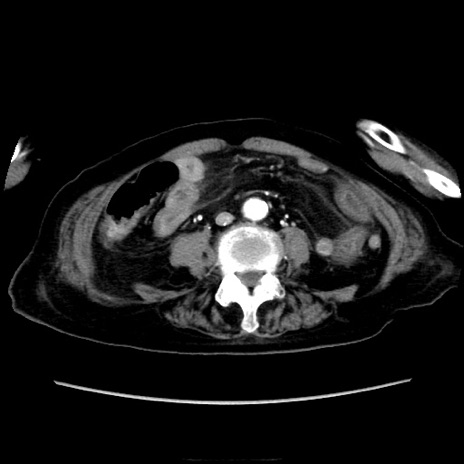

他院CT

横断像

【症例】90歳代女性

【主訴】腹痛・嘔吐

【現病歴】 食欲低下、嘔吐があり昨日他院受診。肺炎と診断され入院となる。入院後より腹部全体に圧痛あり。胃管留置され経過みていたが、症状持続するため、

当院転院となる。

【既往歴】胸椎圧迫骨折、胆石症

【身体所見】腹部:中央に激痛あり、圧痛あり、反跳痛不明

【データ】WBC 17100、CRP 18.82